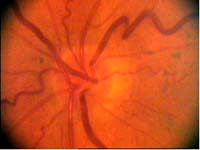

Na dolním pólu terče je patrný zálom vény, která zviditelňuje přítomnost i hloubku exkavace až k dolnímu okraji terče.

V nasálním horním kvadrantu terče vidíme obnažené cévy, které dříve probíhaly v lemu. Toto obnažení může být jedním z prvních příznaků glaukomové neuropathie.